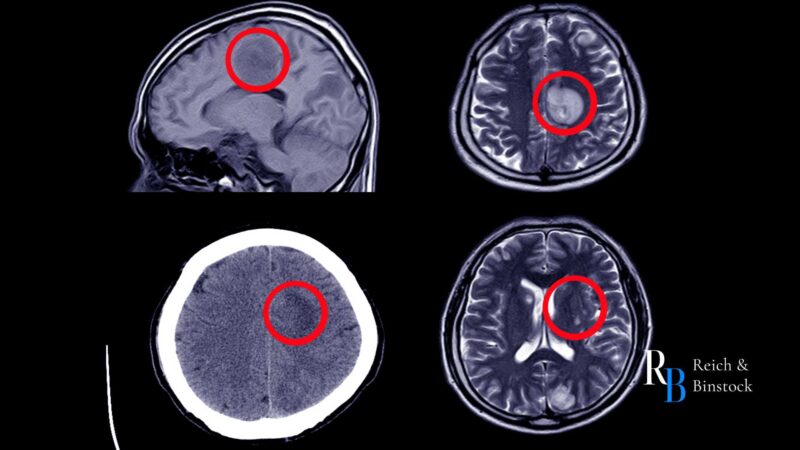

A brain bleed, or intracranial hemorrhage, can cause life-threatening pressure on the brain and require emergency care. Understanding the different types of intracranial hemorrhages and the mild and severe symptoms of a brain bleed can help you seek emergency treatment when it matters most.

A brain bleed, or intracranial hemorrhage, is a life-threatening complication that can occur after a fall or blow to the head. When a head injury ruptures blood vessels inside the skull bone, blood fills areas within the brain tissue or between the three membrane layers that protect the brain: the dura mater, arachnoid membrane, and pia mater.

A brain bleed occurs when trauma, such as a car accident, a slip and fall, or a sports injury, causes bleeding inside the skull. This prevents oxygen and nutrients from reaching the brain tissue, resulting in permanent brain damage without prompt treatment.